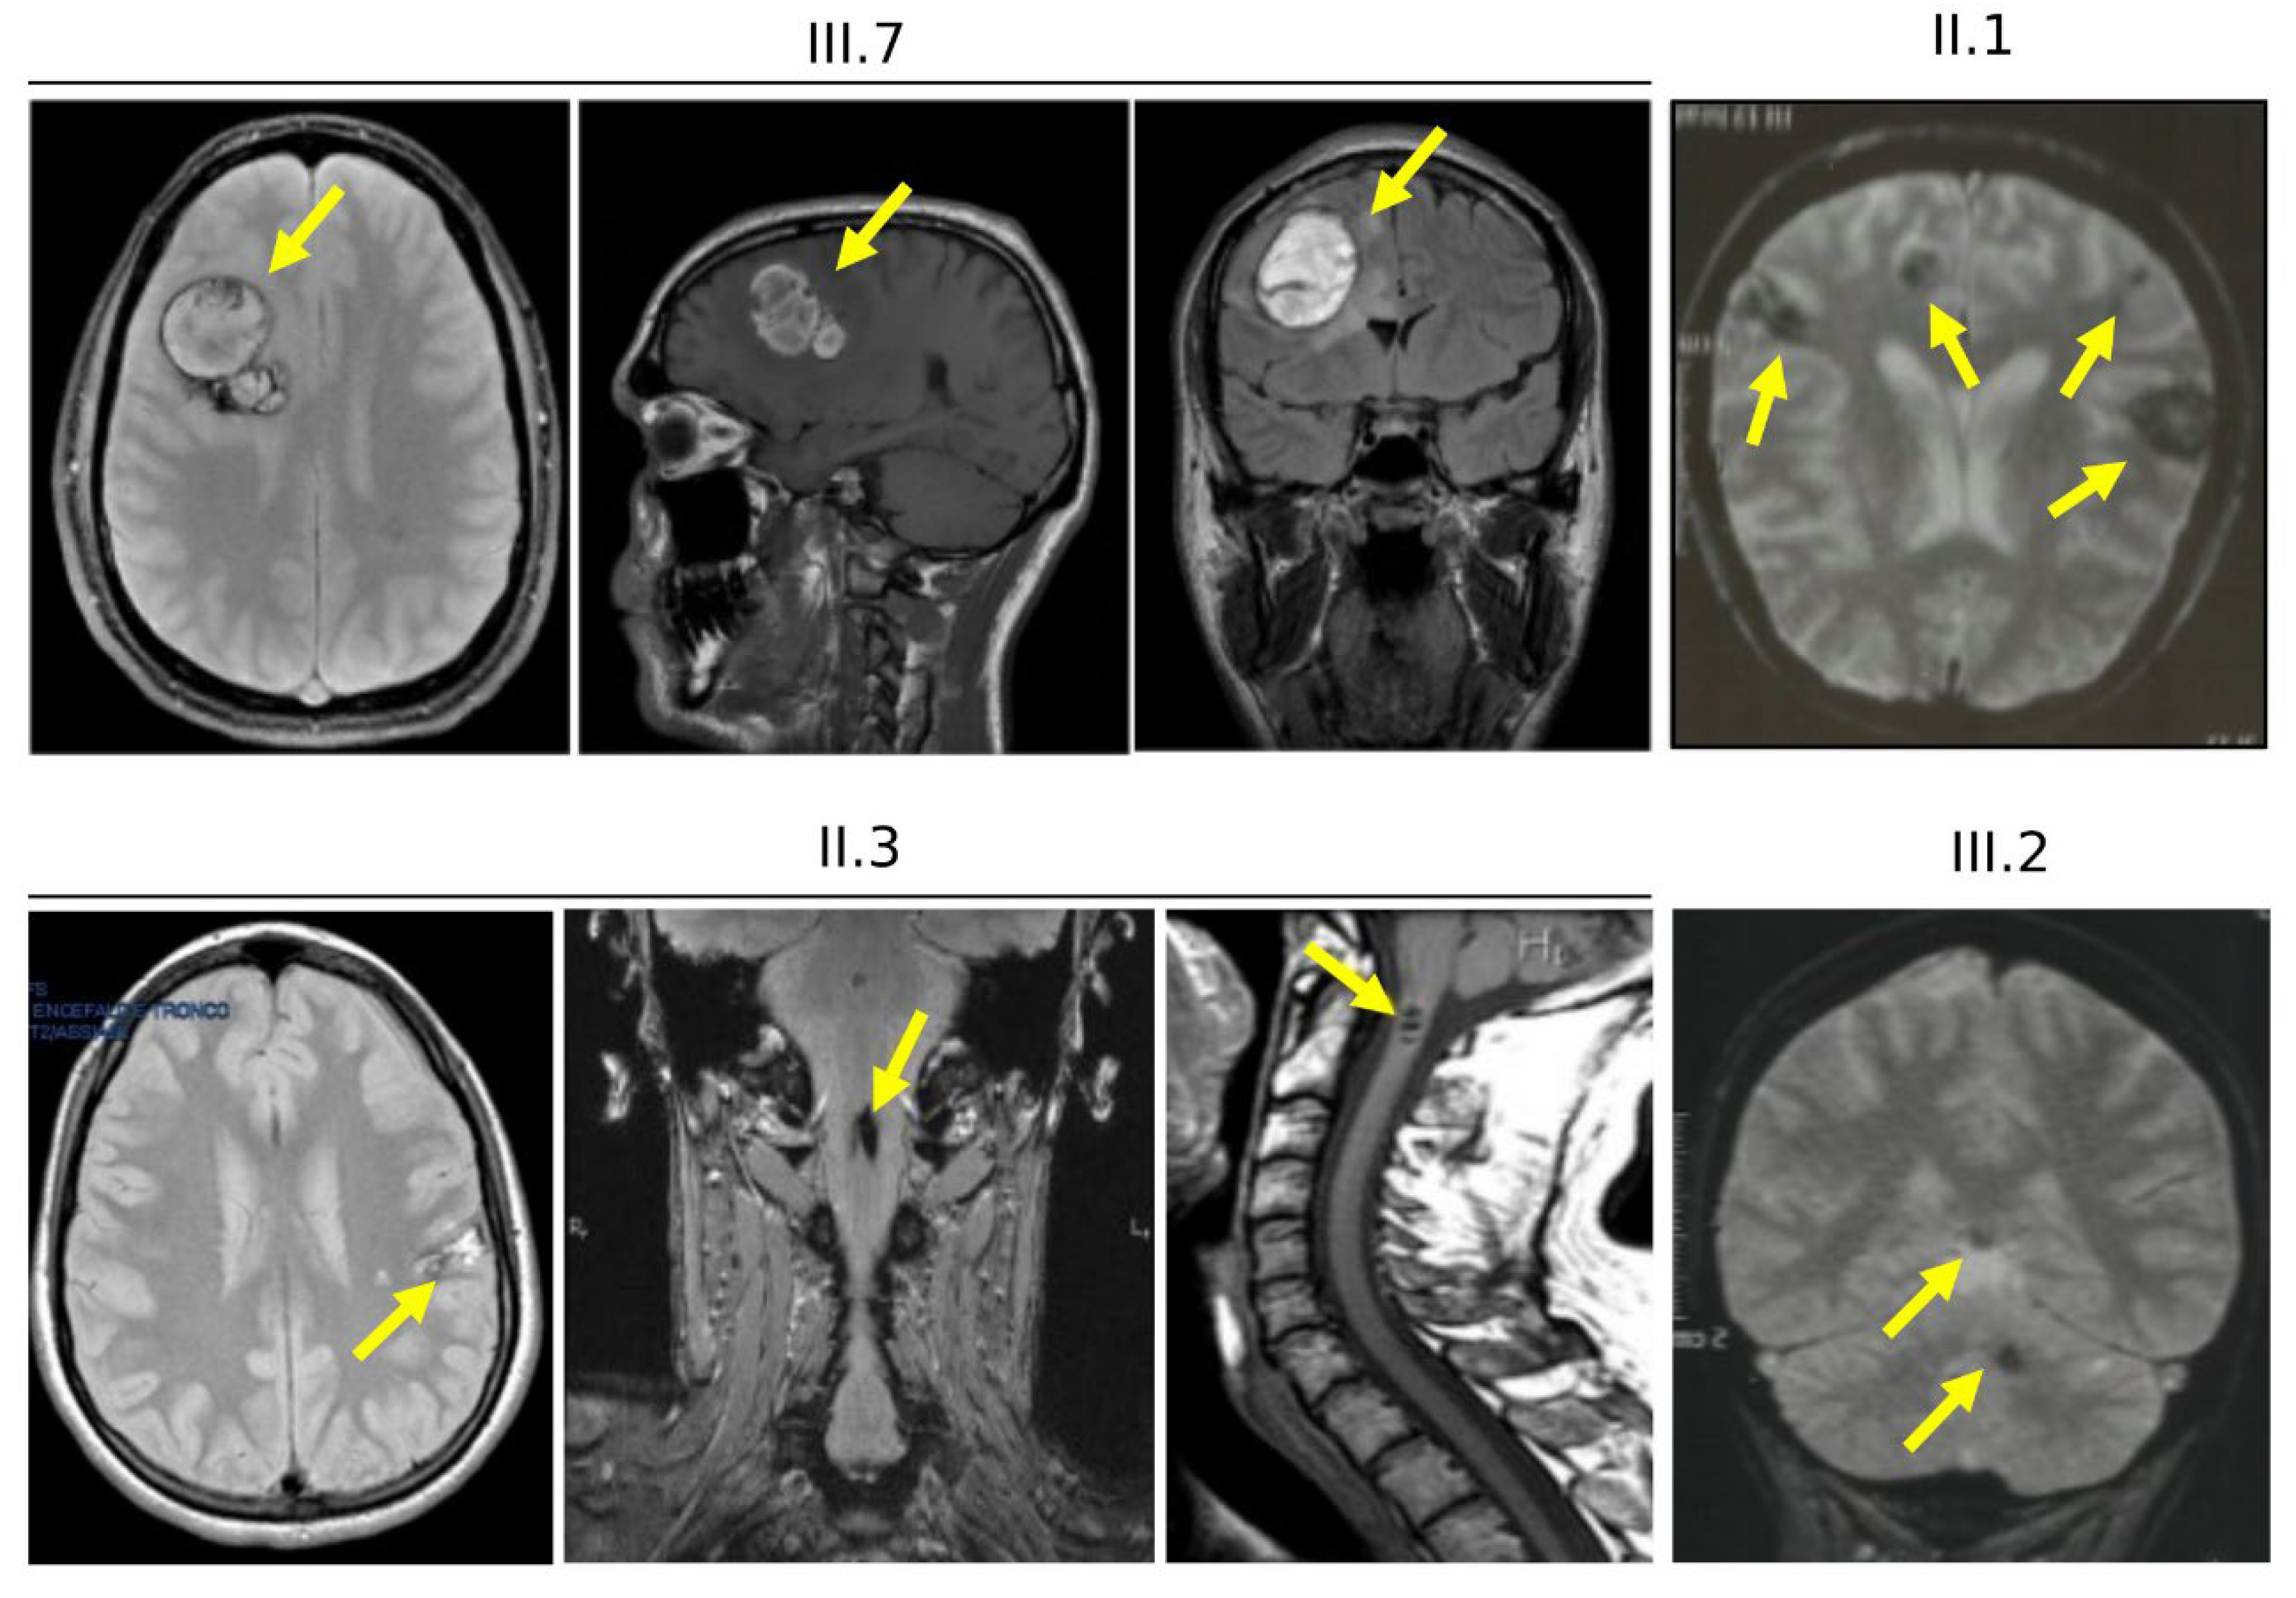

3.4. Clinical Features of Cases Carrying the KRIT1 c.1664C>T Variant (Family 12)

3.6. Clinical Features and Family History of Case #1